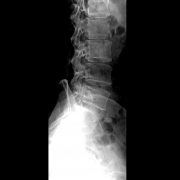

影响X线照片对比度的因素

影响X线照片对比度的因素主要为胶片值、X线质和线量,以及被照体本身的因素。 1. 胶片因素 胶片值,即反差系数,是胶片对X线对比度的放大能力的体现。使用不同值的胶片,所获得的...更多 -